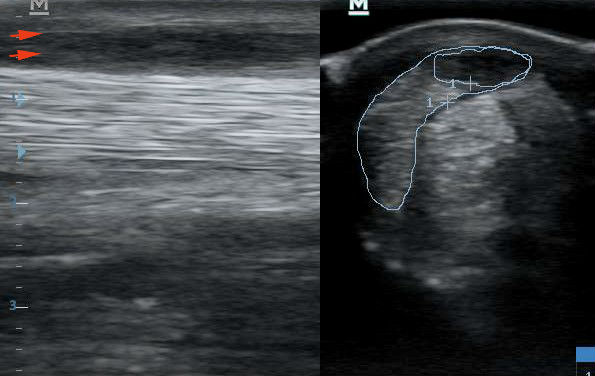

Ezt látjuk a vizsgálat során. Bal oldalon hosszmetszetben, jobb oldalon keresztmetszetben.

Ugyanaz a felvétel, az elváltozások bejelölve. Bal oldalon a piros nyilak jelzik a sérült ín sávját. Az egyenes, erős, fehér csíkok helyén fekete mező. A jobb oldalon körberajzolva az ín teljes keresztmetszete, azon belül a sérült rész. Az erős, fehér pettyezettség helyett fekete mező.